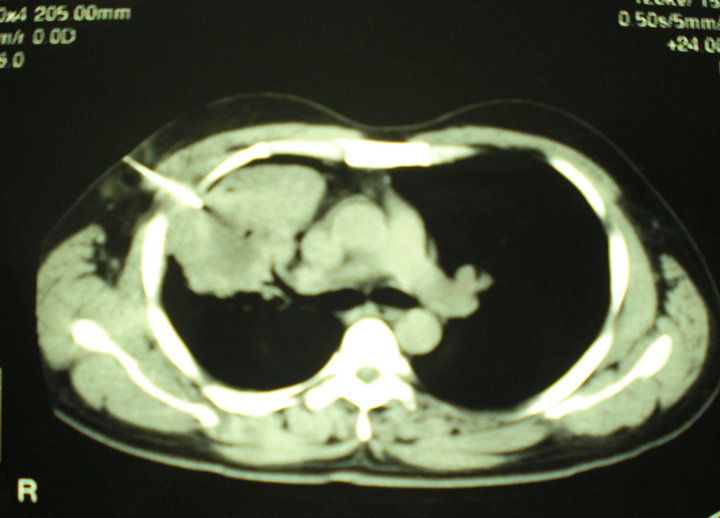

Chest Xray showed a right hilar shadow with speck of cal cifications

Chest Xray showed a right hilar shadow with speck of cal cifications What Is A Shadow On Chest X Ray There are many possible reasons for this. this is usually indicative of a problem, and could be immediately obvious, such as a broken or fractured rib, or could simply be a shadow that needs. Please try not to worry; In fact every radiologst should be an expert in chest film. the shadow in heart, also known as cardiac. What Is A Shadow On Chest X Ray.